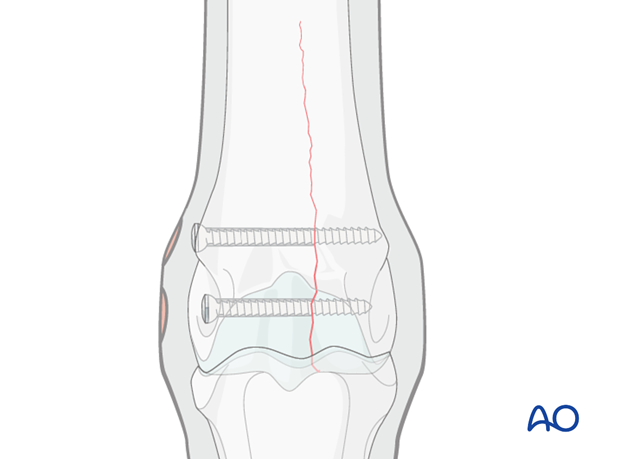

The major principle involved in lag screw fixation of these fractures is compression of the articular surface. Lag screw fixation of the distal portion of the bone may help prevent proximal propagation of the fracture, but definitely does not prevent it. A plate that is securely attached along the rest of the bone effectively helps to prevent catastrophic failure.

Although the glide hole is typically drilled through the smaller fragment and the thread hole across the larger fragment, this particular fracture is often repaired in the opposite manner. The major reason is that it is much safer and easier to approach the leg from the lateral side than the medial side during implant removal, which is routinely performed in the standing position. Fortunately medial condylar fractures tend to be very close to the midline so there is little difference between the width of the two fragments. The bone in this location is so strong, that 25 mm of thread engaged with a 4.5 mm cortex screw is already exceeding the strength of the screw. Therefore, strong fixation can be achieved even though the repair is called “backwards”.

The distal two screws across the condyle are placed routinely through stab incisions under fluoroscopic or radiographic control. It is also desirable to examine the joint arthroscopically to confirm fracture reduction, evaluate joint surfaces and remove any loose fragments. For a detailed description see Medial incomplete condylar fractures - Lag screw fixation.